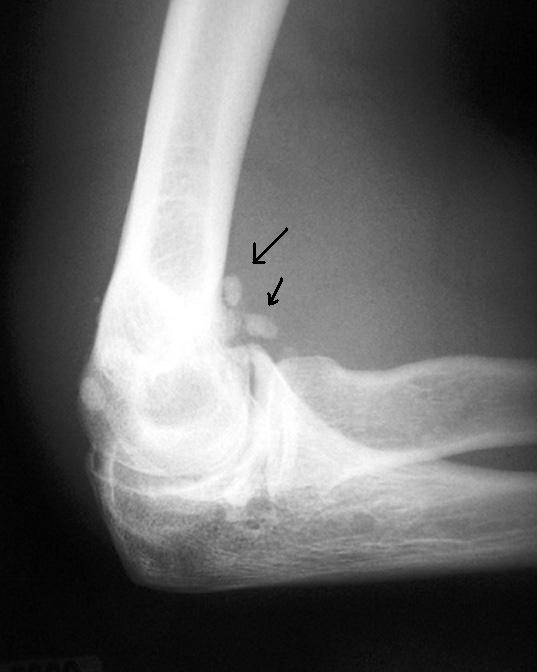

From www.learningradiology.com

Learning Radiology Synovial Osteochondromatosis Synovial Osteochondroma Elbow 2 because the dominant elbow is more commonly. synovial chondromatosis (also called synovial osteochondromatosis) is a rare, benign (noncancerous) condition that involves the synovium, which is the thin layer of tissue that lines the joints. synovial chondromatosis (sc) is a benign uncommon condition of the synovial membrane of joints, tendon sheaths, and bursae that can result in. . Synovial Osteochondroma Elbow.